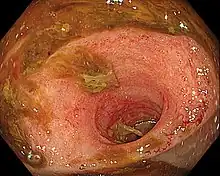

| Ileitis caused by capecitabine. | |

Ileitis is an inflammation of the ileum, a portion of the small intestine. Crohn's disease is the traditional cause of ileitis. Ileitis, however, may be linked to a broad range of illnesses. These comprise a range of illnesses, such as sarcoidosis, amyloidosis, ischemia, neoplasms, spondyloarthropathies, vasculitides, drug-related conditions, and eosinophilic enteritis.[1]